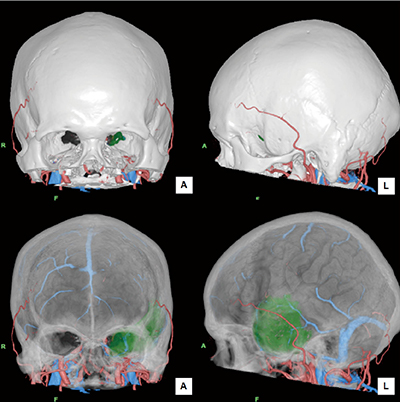

2)脳腫瘍術前精査

脳神経外科の脳腫瘍術前精査では、必ずCTとMRIを施行し、CT perfusionでは脳腫瘍と栄養血管の位置関係と血流動態を把握することを目的とする。MRIではtractography、3D-FLAIR、MR DSA、MR perfusionを撮像し、脳腫瘍と神経線維の位置関係および血流動態を把握することを目的としている。CTでは動脈・静脈を個々に抽出し、MRIでは腫瘍抽出、tractographyによる錐体路の描出をする。これらをFusionすることで、血管と腫瘍および神経線維の情報を任意の方向から作成することが可能となる(図2)。CTの頭蓋骨の画像と3D-FLAIRの脳表画像をFusionし、頭蓋骨の透過度を変化させることで、脳実質内の腫瘍の位置や手術時のアプローチなどを決定する際の有用な情報となる(図3)。

図2 動脈・静脈・腫瘍・椎体路のFusion画像

図3 骨・脳表のFusion画像